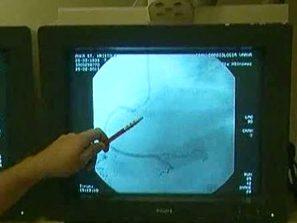

В момента у нас се прави ангиопластика на 35-40 на сто от пациентите, докато в страните от Европейския съюз тя се прилага при 90% от случаите.

- Тези болници правят ангиопластики на много спешни пациенти, това е много добре за хора и много важно и аз мисля, че трябва да продължава.